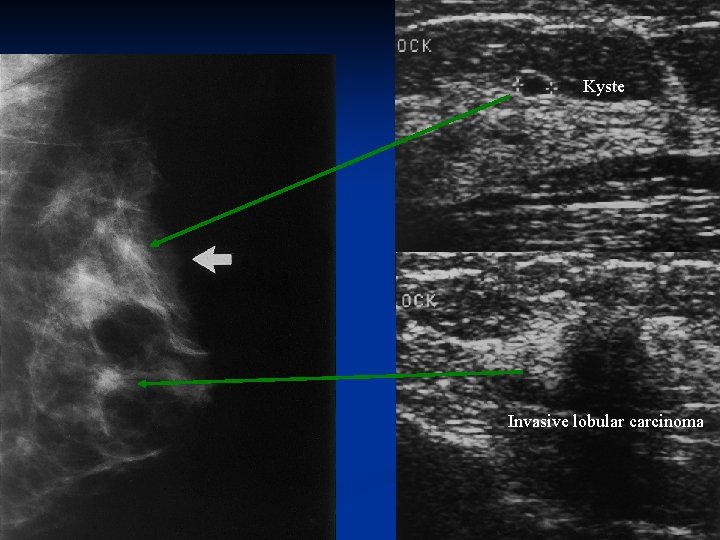

Kyste Invasive lobular carcinoma